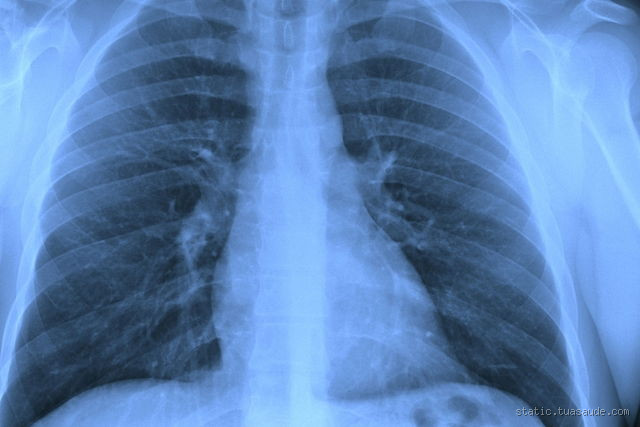

O raio-X de tórax é geralmente o primeiro exame solicitado. Ele permite ver se há um aumento de fluido nos pulmões ou sinais de inchaço.

Se houver líquido nos pulmões, o raio-X pode mostrar áreas esbranquiçadas ou opacas, indicando a presença de fluido.